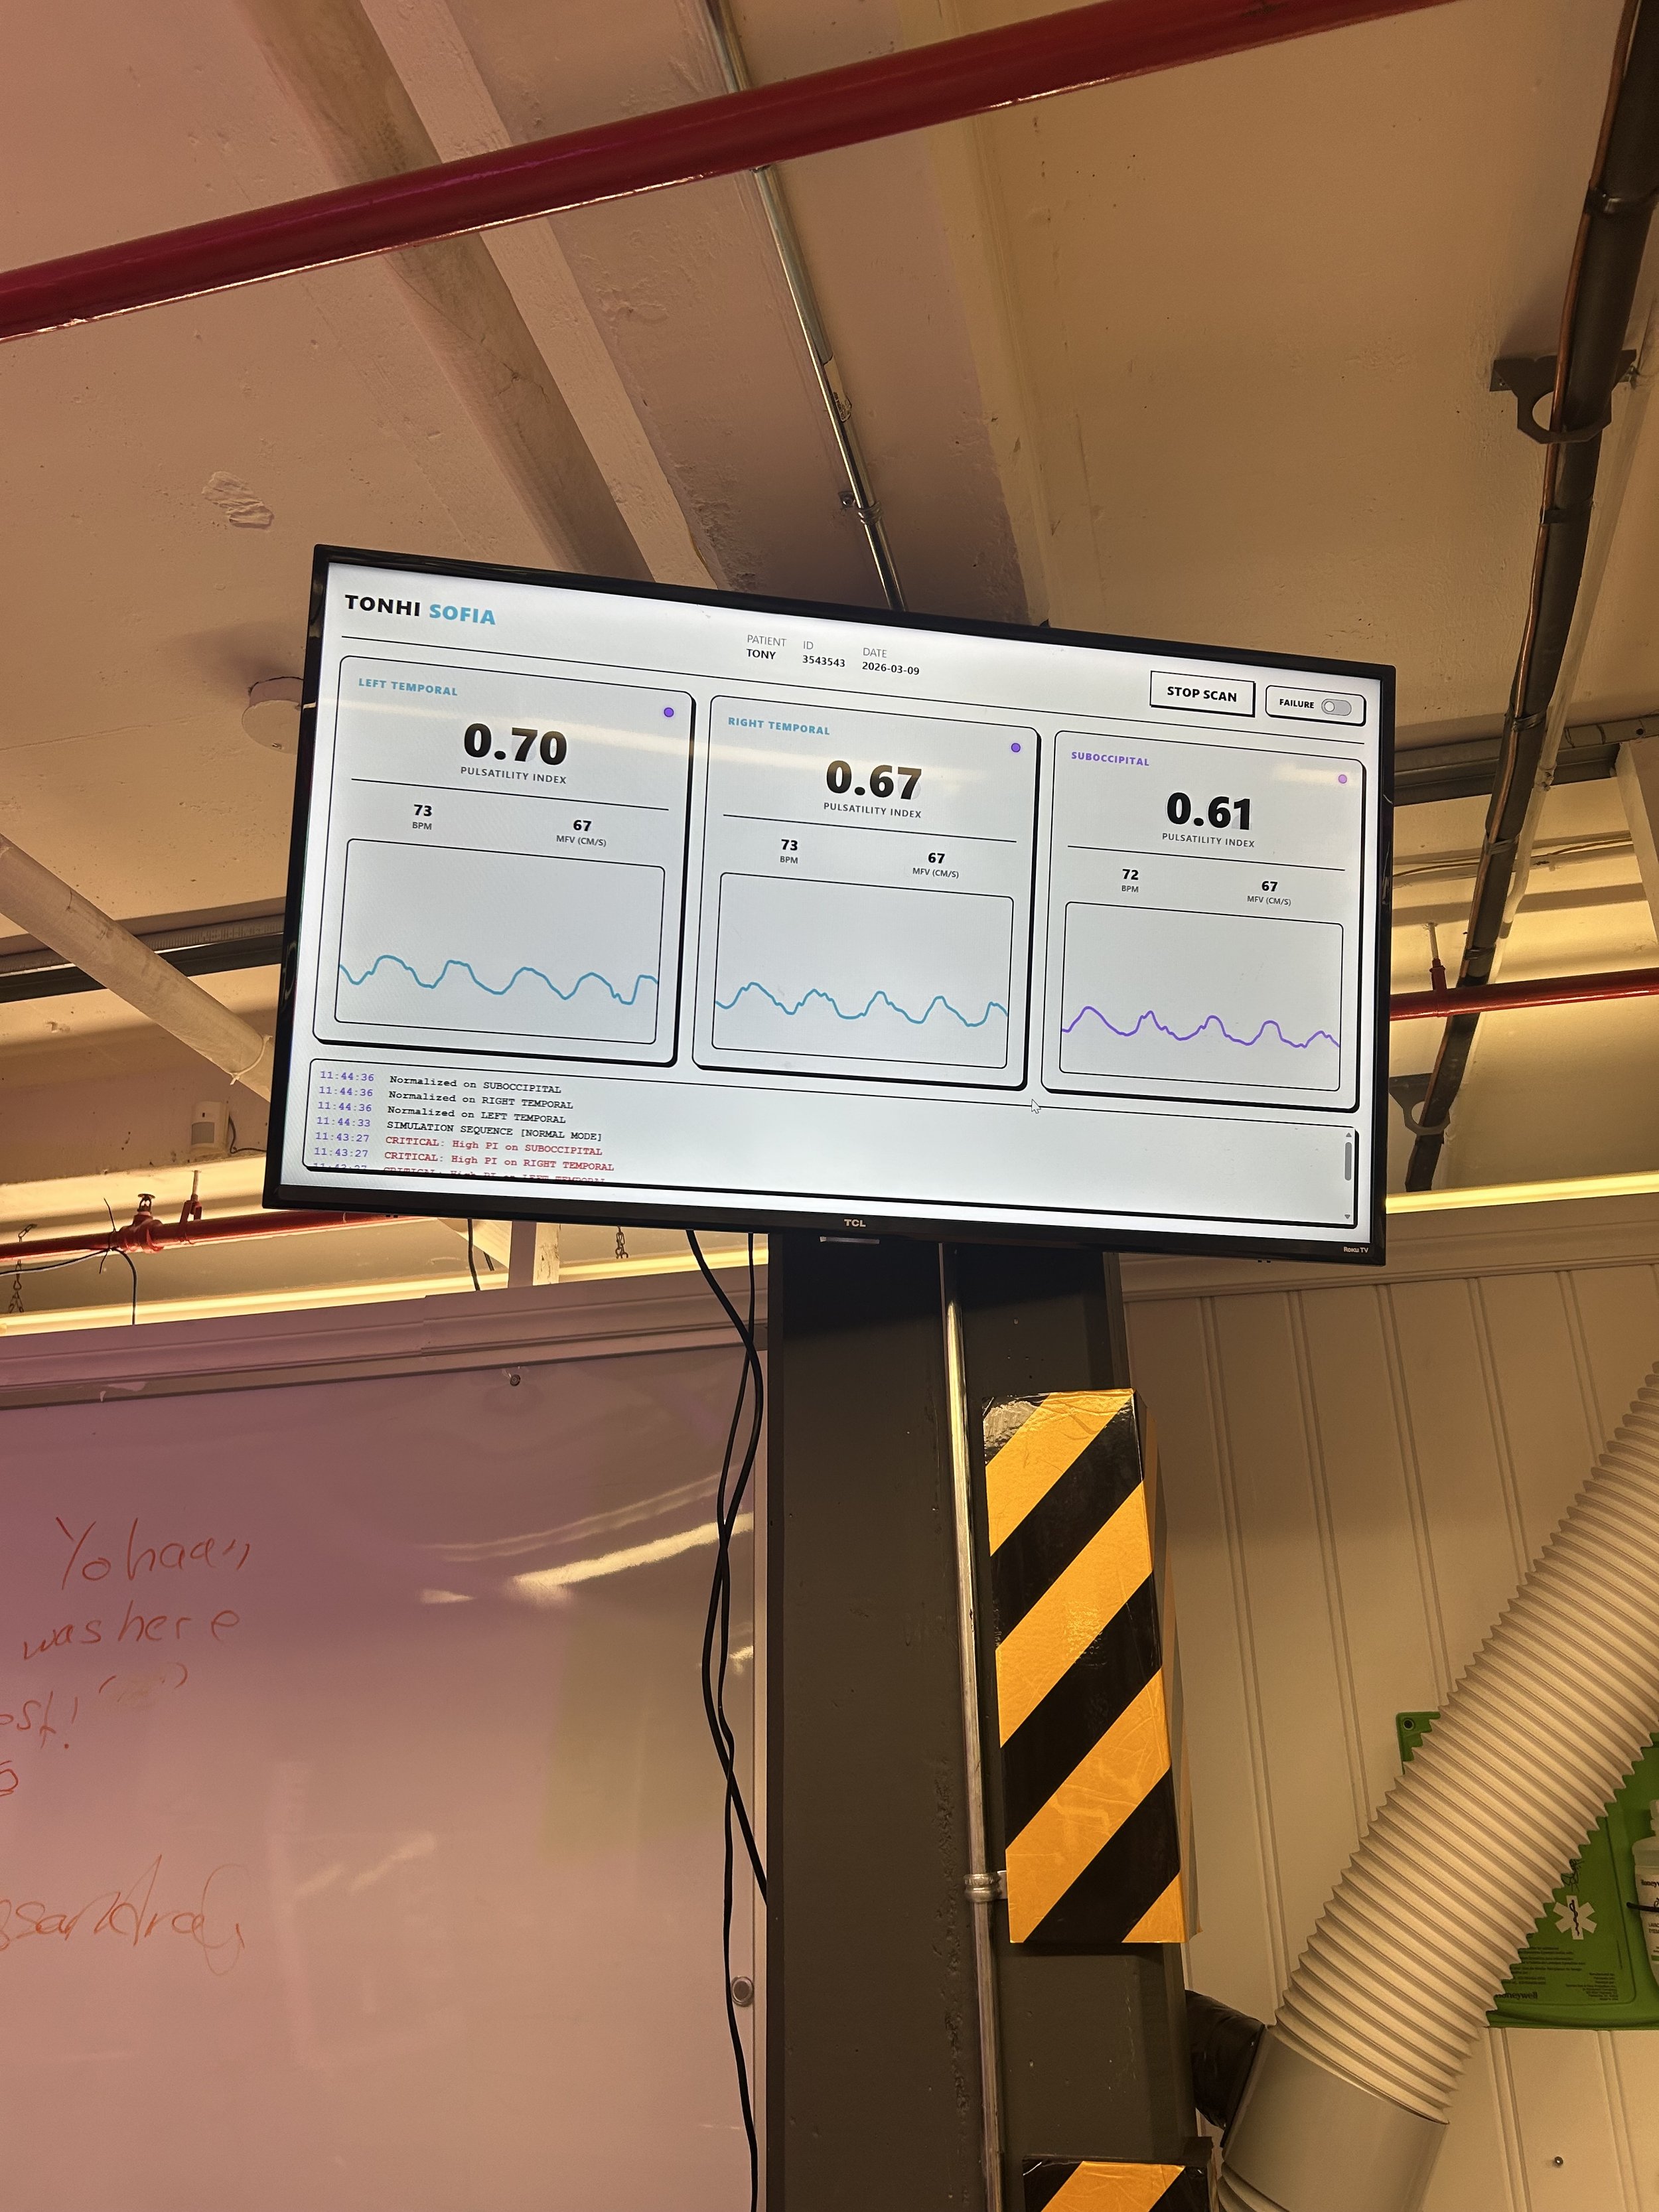

With the TONHI technology, it is possible to read intracranial pressure to predict whether or not a symptom is telling of a hydrocephalus ‘episode’. Instead of focusing on precautionary technology for the condition, TONHI strives to create a reliable, life-saving reactionary device that will quickly tell them if they are in need of another shunt replacement. To accomplish this, TONHI uses transcranial doppler ultrasounds to gather information used to calculate pressure and transmits the information into an app; if the pressure is above the patient’s baseline and they are experiencing symptoms, medical attention is required.

Transcranial ultrasound dopplers will be placed at both transtemporal lobes and the suboccipital lobe of the patient to capture blood flow information and intracranial pressure.

Once the patient has used TONHI, they will get immediate results in a mobile app as waveforms. This is will show them if there has been an intracranial pressure increase.